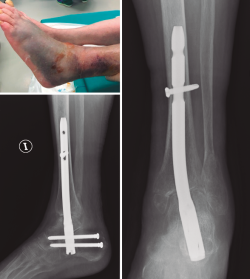

Buscando los objetivos deseables en el anciano frágil de aportar una estabilidad primaria suficiente que permita la carga temprana, en una sola cirugía y con la menor agresión posible, varios estudios han publicado sus experiencias tratando este tipo de fractura en casos seleccionados mediante el uso de enclavado retrógrado TTC(12,61,62,63,64,65)(Figura 6).

Figura 6. Clavo tibiotalocalcáneo en paciente diabética con baja demanda funcional y mal estado de partes blandas.

Lemon(61) en 2005 publica el primer artículo utilizando clavos, en lugar de Steinmann transarticulares, para la estabilización indirecta de fracturas inestables de tobillo en el anciano. En su serie de 12 pacientes, con edad promedio de 84 años, todos los pacientes iniciaron la carga completa el primer día postoperatorio, no presentando complicaciones óseas ni de partes blandas y consiguiendo en la mayoría de los casos la situación funcional previa.

En 2014, Al-Nammari(62) publica una serie de 48 pacientes frágiles, de edad promedio de 82 años, tratados mediante enclavado TTC usando un clavo largo de fémur, ya que este autor recomienda pasar el istmo de la tibia con el implante para evitar posibles fracturas periimplante con clavos cortos. La mortalidad a los 6 meses fue del 35%, pero el 90% de los pacientes restantes recuperaron la situación funcional previa. Entre las complicaciones, presentaron un 6% de infecciones, un 6% de rotura o aflojamiento de tornillos distales, un 4% de consolidación en mala posición no sintomática y un caso de amputación infrageniana en un paciente con fractura abierta IIIC. No presentaron ningún caso de pseudoartrosis, rotura del clavo ni fractura periimplante. En este estudio retrospectivo, el autor, aunque refiere que la decisión para este tratamiento fue esencialmente subjetiva, sin criterios de inclusión establecidos, sí define factores que pueden influir para la elección de este tratamiento: 1) pacientes con deambulación limitada a domicilio o menor de 200 metros precisando ayudas; 2) pacientes física o mentalmente demasiado frágiles como para tolerar la restricción de carga; 3) mala calidad ósea y/o de partes blandas; 4) puntuación de la American Society of Anaesthesiologists (ASA) de 3 o más; y 5) comorbilidades significativas(62). Otros factores descritos en otros artículos(12,63) que podríamos incluir para la toma de decisión serían: 6) presencia de diabetes y/o neuropatía y/o vasculopatía periférica; 7) fracturas abiertas; y 8) angulación del eje de más de 15° en al menos una proyección.

Otros estudios más recientes, tanto con clavos cortos(63,64) como largos(65) TTC, para el tratamiento de fracturas inestables de tobillo en pacientes frágiles con baja demanda funcional, presentan buenos resultados funcionales, con carga completa temprana y con bajas tasas de complicaciones, sin presentar fracturas periimplante con un seguimiento mínimo de un año. Como consideraciones técnicas cabe resaltar que no se precisa la cruentación articular ni la retirada del implante(62,63,64,65) y el tiempo medio de cirugía puede ser de 55 minutos(62).

Georgiannos(64) publica el único estudio prospectivo comparativo aleatorizado hasta la fecha, comparando la osteosíntesis convencional (manteniendo en descarga 6 semanas) con el clavo corto TTC (con carga completa según la tolerancia) en 87 pacientes mayores de 70 años con fracturas cerradas bi- o trimaleolares y fracturas-luxaciones, independientemente de la situación funcional previa (a diferencia de estudios previos). Excluye del estudio los pacientes con fracturas abiertas, fracturas de alta energía, demencia, vasculopatía periférica severa o angiopatía diabética. La mortalidad al año fue similar en ambos grupos (14-18%). No encontraron diferencias significativas en cuanto al retorno a la situación funcional previa (72-75%), si bien el índice de trombosis venosa profunda y la estancia hospitalaria fue significativamente menor en el grupo del clavo TTC. También el porcentaje de infecciones y de reintervención quirúrgica fue menor en el grupo del clavo TTC, pero sin significación estadística. El autor concluye que en pacientes ancianos frágiles el clavo TTC es un método seguro y efectivo, que reduce la agresión y el riesgo de complicaciones, y permite la carga completa inmediata.